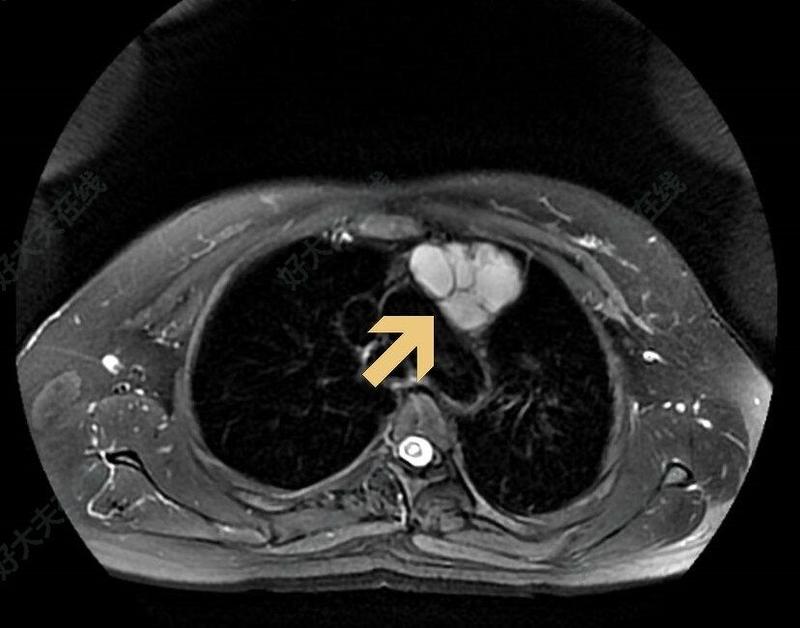

體檢發(fā)現(xiàn)前縱膈腫物,比較重要的檢查有胸部增強(qiáng)CT和磁共振檢查。胸部增強(qiáng)CT:了解瘤體和周圍器官(如:重要血管)的關(guān)系,醫(yī)生便于評估手術(shù)難度、制定“作戰(zhàn)計(jì)劃”;磁共振:可以分辨是實(shí)性腫瘤?還是囊性腫物(“一包水”)?1實(shí)性腫瘤往往建議積極手術(shù),較大者往往侵犯周圍重要組織器官,手術(shù)復(fù)雜程度還有疾病嚴(yán)重程度都可術(shù)前預(yù)判2囊腫則預(yù)判手術(shù)不那么緊迫,可以視瘤體大小決定手術(shù)時(shí)機(jī),往往侵犯力、手術(shù)復(fù)雜度比實(shí)性腫瘤好。